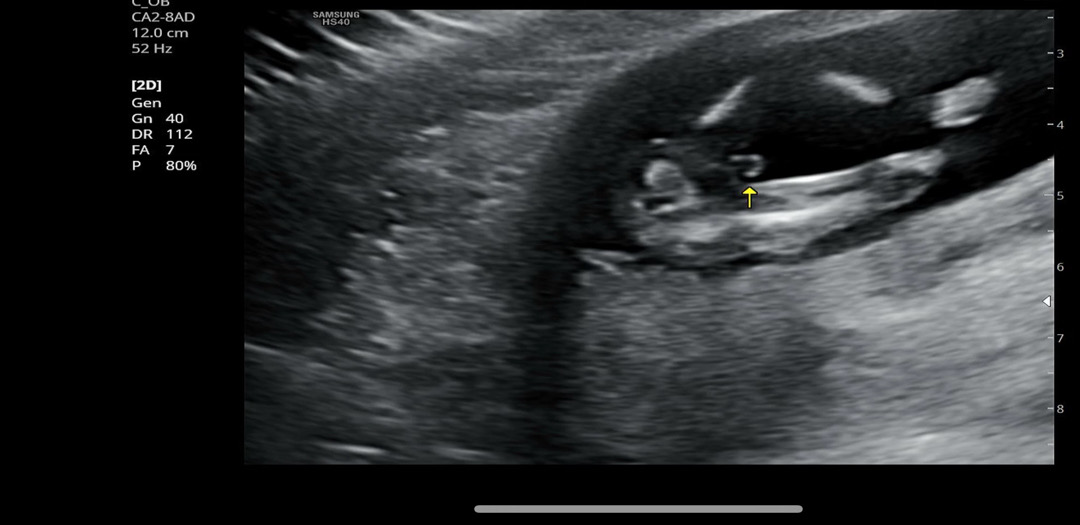

14주3일 초음파 아들 맞을까요-?!

다리 사이에 있는게 🌶️ 고추가 맞을까요?! 넘넘 궁금해요!!💕

아들이네요!

넹 맞는거같아용